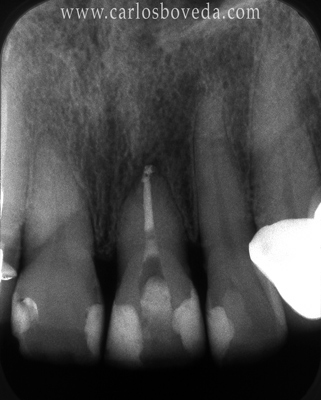

17